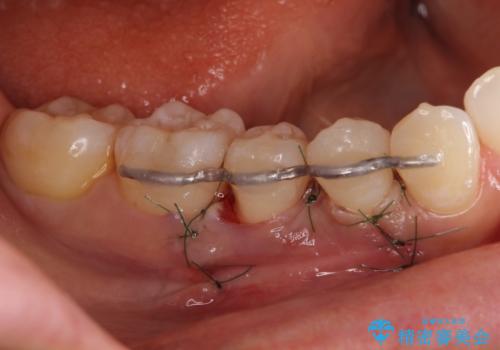

骨の再生治療手術をして10か月経過観察をしたのち、骨を平坦化する手術を行い、治療終了となりました。

・手術後はしばらくワイヤー等で固定する必要があります。